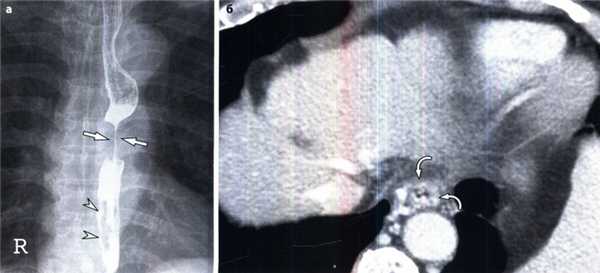

Варикозное расширение вен пищевода с восходящим кровотоком у мужчины 68 лет с раком пищевода.

(а) Выявлена циркулярная инфильтрация срединного отдела пищевода опухолью (стрелки), варикозные расширения представлены извилистыми дефектами наполнения в дистальном отделе пищевода (указатели).

(б) При КТ с контрастным усилением в поперечной проекции установлены цирротическое поражение печени и выраженное варикозное расширение (изогнутые стрелки) в дистальном отделе пищевода.